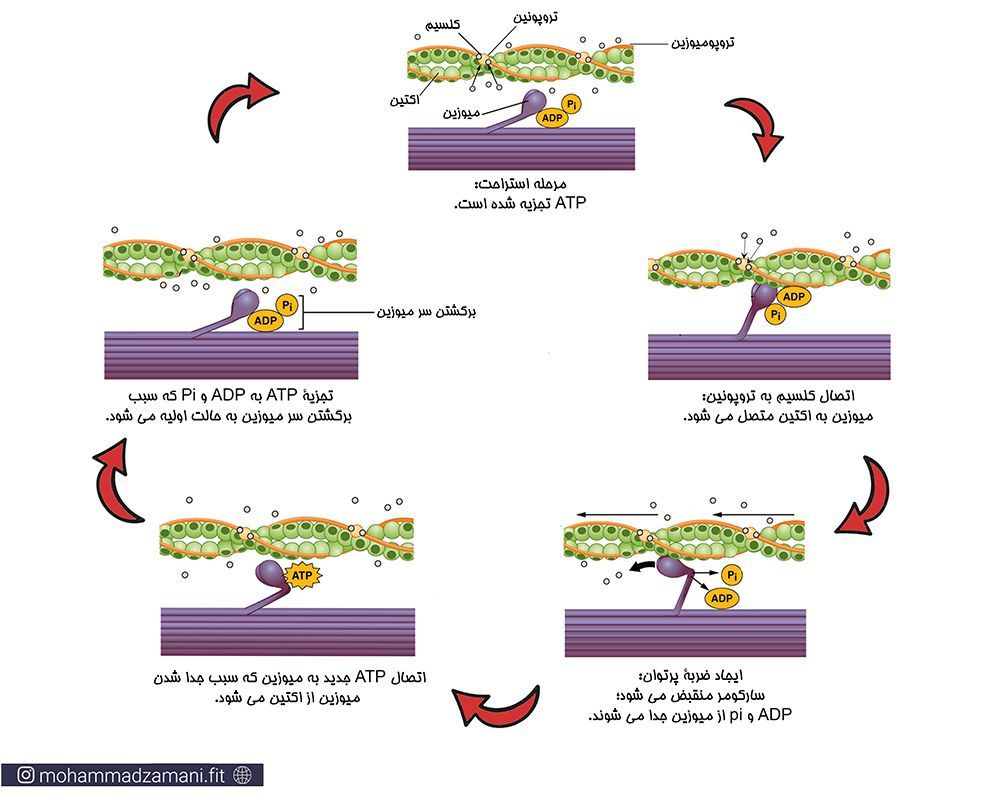

دستگاه حرکتی

گفته که توی بخش روشن سارکومر رشته های اکتین رو داریم

سوال من اینه که نمی تونیم بگیم یه منطقه روشن دیگه هم اون وسط داریم و اونمنطقه روشن فقط شامل میوزینه؟

گفته که توی بخش روشن سارکومر رشته های اکتین رو داریم

سوال من اینه که نمی تونیم بگیم یه منطقه روشن دیگه هم اون وسط داریم و اونمنطقه روشن فقط شامل میوزینه؟

سلام درسته در واقع اونجا ما منطقه روشنی داریم که میوزین هست اما تاجایی که یادمه تو تحتانی در نظر نمیگرفتند و همون علامت گذاری کتاب برای منطقه روشن و تیره رو مبنا قرار میدادن. ولی از لحاظ علمی حرفت درسته.

همین منطقه روشن وسطپرستو بابایی من متوجه سوالت نشدم ولی خب اخه مگه ما نمی گیم قسمت های نزدیک خطوط زد میشه اکتین ها و اون بخش سفیدی که به خط ام وصله رو هم فاقد اکتین می گیریم و برا همین قطعا غلطه دیگه چون تعریف کروی رو فقط برای اکیتن ها می گیریم. یا اگه مبحث دوازدهم ترکیب داره من نمیدانم🥲

گفته که توی بخش روشن سارکومر رشته های اکتین رو داریم

سوال من اینه که نمی تونیم بگیم یه منطقه روشن دیگه هم اون وسط داریم و اونمنطقه روشن فقط شامل میوزینه؟

متوجهید؟پرستو بابایی دقیقا منم همین ایده رو دارم. اما الان یادم اومدن اون بخش رو باید تیره بگیریم.یعنی اونجا رو بخش روشن نمی گیریم.برا همین درست شده.

گفته که توی بخش روشن سارکومر رشته های اکتین رو داریم

سوال من اینه که نمی تونیم بگیم یه منطقه روشن دیگه هم اون وسط داریم و اونمنطقه روشن فقط شامل میوزینه؟

ولی خب چون خوده کتاب کلا اونجارو بصورت منطقه تیره در نظر گرفته دیگه اینطوریه -